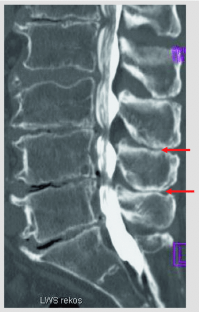

Abb. 3